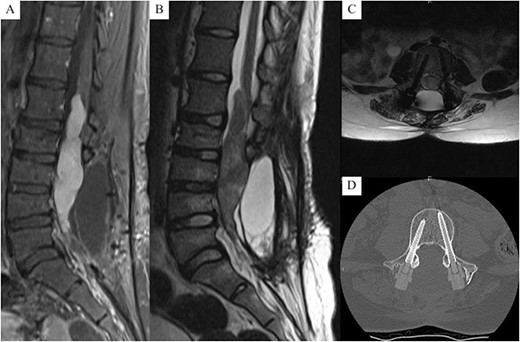

Subsequent imaging demonstrated an intradural tumour spanning L1–L5 vertebral levels, involving the conus and lower sacral nerves (Fig. 1). She underwent resection of the tumour, followed by T12 and L1 laminoplasty and revision of her previous L2–S1 fusion. T12–S1 was exposed, and previous CF/PEEK pedicle screws from L2 to L4 were removed. A T12 and L1 laminectomy was performed, with posterior elements preserved for re-implantation. However, it was decided that the laminae would be replaced with CF/PEEK pedicle screws as well. A midline durotomy was made, and an arachnoid specimen was sent for histopathological analysis. The tumour was removed piecemeal with sacrifice of several nerve roots.

(A) T1 with contrast mid-sagittal MRI, (B) T2 mid-sagittal MRI, (C) T2 axial MRI at L4, (D) axial CT at L4 (bone window), demonstrating a L1 - L5 intradural tumour with significant cauda equina compression; no signal interference or artefacts from the screw construct are present, allowing clear visualisation of the vertebral body and canal.